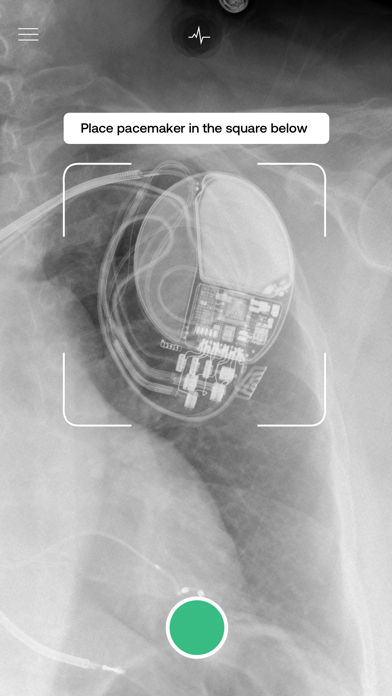

Pacemaker-ID uses a deep-learning model to determine the manufacturer of a given pacemaker and defibrillator in an x-ray image.